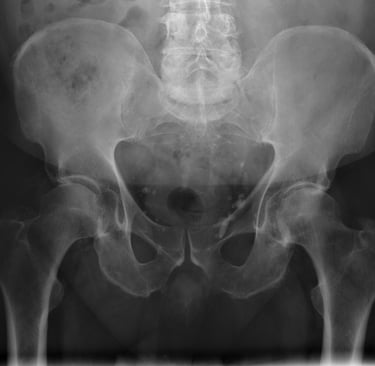

Para determinar la causa exacta del dolor, se realiza una evaluación clínica detallada, analizando la movilidad, la estabilidad asi como pruebas especificas para identificar las causas probables del dolor. En muchos casos, se complementa el diagnóstico con estudios de imagen para observar el estado de los huesos, los cartílagos y los tejidos blandos, así como pruebas de laboratorio en caso de sospecha de enfermedades inflamatorias o metabólicas.